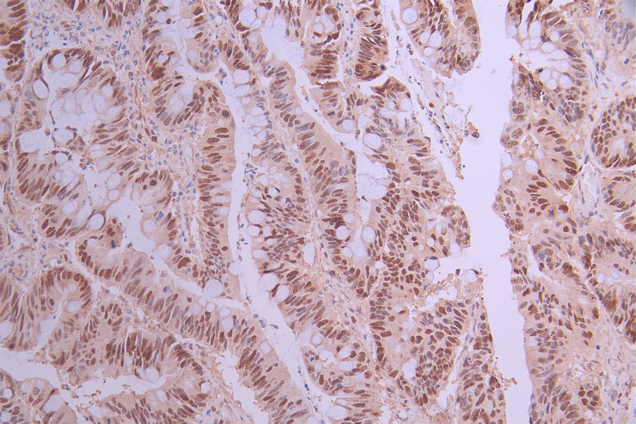

IHC image of CSB-RA699720A0HU diluted at 1:100 and staining in paraffin-embedded human colorectal cancer performed on a Leica BondTM system. After dewaxing and hydration, antigen retrieval was mediated by high pressure in a citrate buffer (pH 6.0). Section was blocked with 10% normal goat serum 30min at RT. Then primary antibody (1% BSA) was incubated at 4°C overnight. The primary is detected by a Goat anti-rabbit polymer IgG labeled by HRP and visualized using 0.05% DAB.